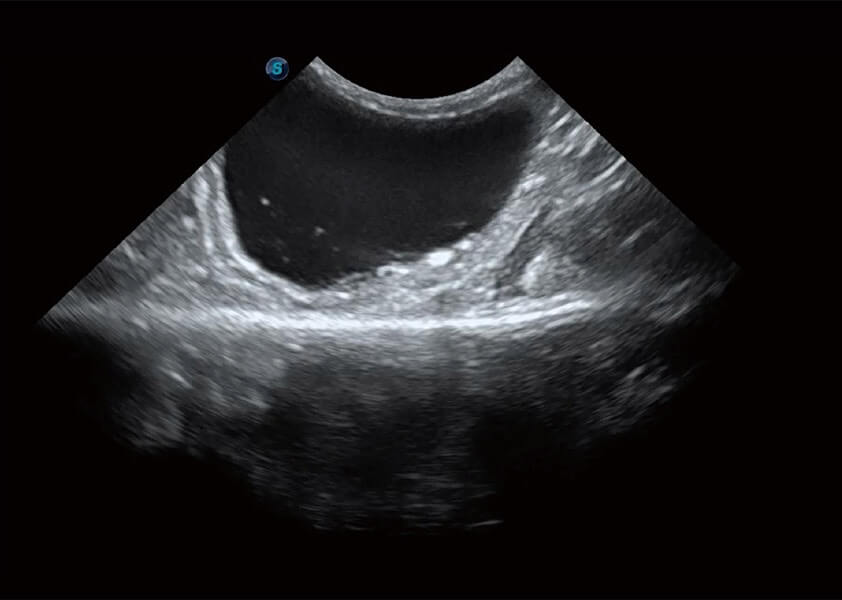

ProPet 60 作为一款高端台式动物超声设备,为动物医生的日常诊断提供了一系列贴合动物临床需求、解决临床实际问题的高级成像功能。凭借全系列高清探头,满足医生对腹部、心脏、生殖、浅表、肌骨等成像的所有需求,切实帮助您提升检查效率,提高诊断信心。